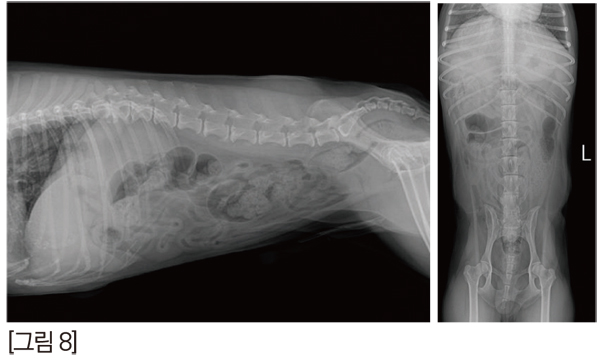

방사선 검사에서도 큰 이상이 없어서 초음파 검사를 진행하였습니다. [그림 8]